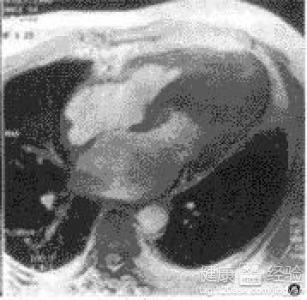

摘要:關(guān)于擴張性心肌病的最新治療,小巷深處的隱藏寶藏正逐漸為人們所發(fā)現(xiàn)。通過先進的醫(yī)療技術(shù)和方法,擴張性心肌病的治療取得了新的進展。這些治療方法旨在改善心臟功能,提高患者生活質(zhì)量。小巷深處的醫(yī)療機構(gòu)或?qū)<铱赡茈[藏著寶貴的治療經(jīng)驗和方法,為尋求最佳治療方案的病患帶來希望。更多詳細信息需要進一步探索和研究。

你將了解到最新的藥物治療、心臟康復計劃以及生活方式調(diào)整等方面的知識?!靶闹蹫场边€開展了一系列臨床試驗,為患者提供最新的治療方案,他們的治療方法全面且個性化,因為每個患者的狀況都是獨特的,所以需要因人而異定制治療方案。